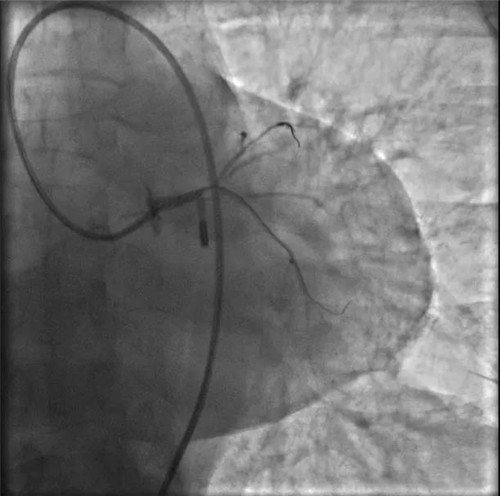

IABP(主動脈內球囊反搏)

突發(fā)的狀況并沒有打亂團隊的陣腳,待生命體征穩(wěn)定后,決定先植入IABP(主動脈內球囊反搏)提供循環(huán)支持,防止病情進一步惡化。穿刺雙側股動脈,分別置入IABP導管及左冠指引導管。

因患者股動脈扭曲,導管操控困難,術者反復嘗試,以導絲飄進左主干,在球囊的支撐下,通過閉塞段到達中間支,小壓力擴張后造影可見主干末端嚴重狹窄。隨后小心操控導絲到達回旋支、前降支,送入球囊擴張,嚴重狹窄的左主干末端被撐開,左冠血流終于恢復,胡女士暫時轉危為安。

球囊擴張后,左冠血流恢復,但左主干末端重度狹窄